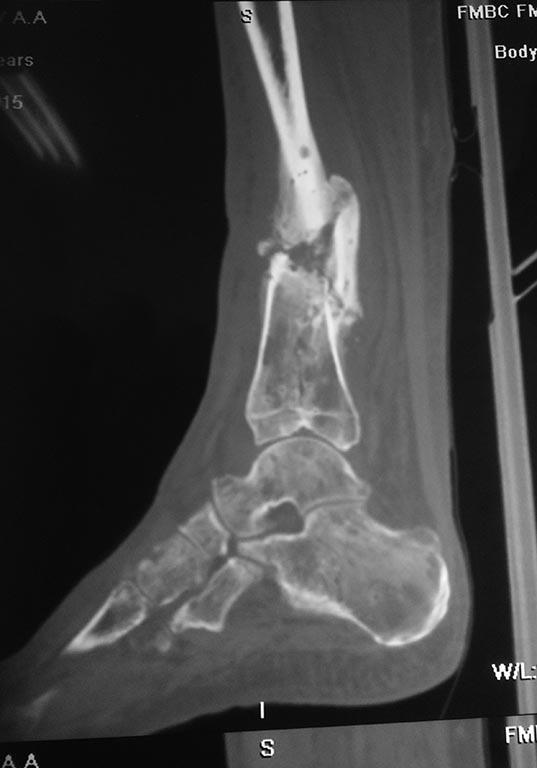

Небольшое уточнение: оперирован 1 августа, в ноябре снята база со стопы, в конце декабря демонтаж аппарата. Показания к снятию аппарата- заключение рентгенолога - консолидирующийся перелом, отсутствие патологической подвижности. Рана заживала около 3 -х месяцев условно первичным натяжением. Так как нет КТ руководствовались в основном рентген снимками.

Снимки при поступлении, спустя 2,5 месяца. Рентген снимки после снятия аппарата в архиве пришлю позже. Осылаю КТ от апреля.

У нас практически нет опыта лечения осложненных переломов. С учётом повреждения мягких тканей, избыточной костной мозоли очень хочется применить штифт( есть мнение что не хватило механики, а с биологией все хорошо). Ранняя нагрузка, нетравматичность более предпочтительней в данном случае? Там ещё не совсем ясно что с медиальной лодыжкой,на КТ Пишут что перелом не консолидированный. Возможно ли направить пациента на консультацию в пределах Москвы и МО кто занимается данной патологией?